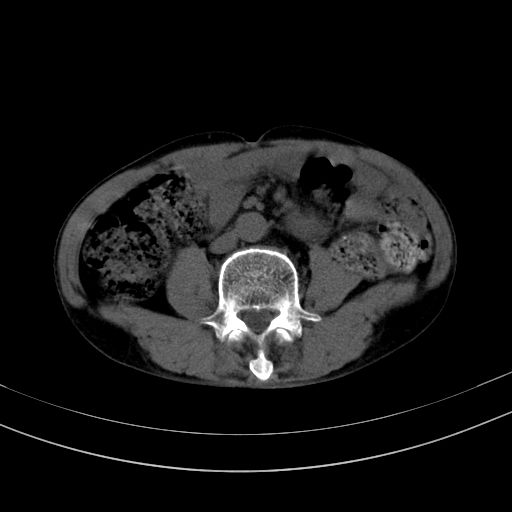

以下是引用37度在2010-1-9 14:37:00的发言:[br]1.双肾囊肿,左肾积水结石,.胆总管轻度扩张;[br]2.病灶在腹膜外,考虑纤维瘤。

以下是引用dyqct在2010-1-9 17:56:00的发言:[br]考虑:1.双肾囊肿,左肾积水结石、旋转不良。[br] 2.右侧腹直肌血肿或纤维瘤。[br]肠道准备不好。做个增强。